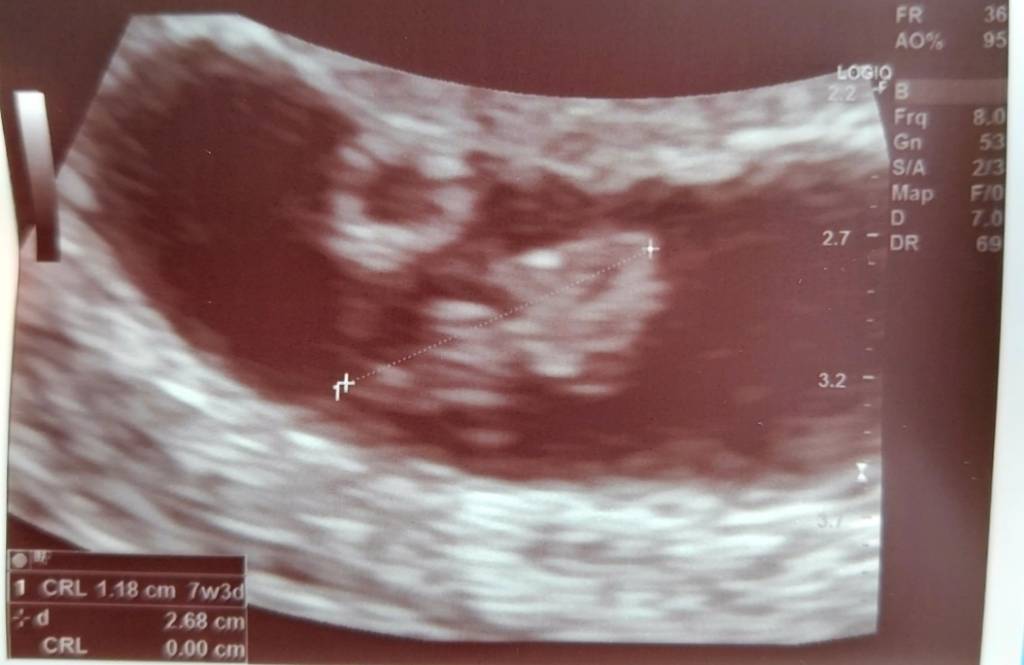

Hej! Wczoraj miałam USG, dzidzia rośnie prawidłowo, serduszko bije jak dzwon [emoji2] z usg wychodzi mi dzisiaj 7+4, termin 03.04.

@Chocolate1, pytałam o nieregularny kształt pęcherzyka, lekarz mówił że u mnie jest wszystko OK i że ten kształt pęcherzyków lubi się zmieniać, więc mam nadzieję, że u Ciebie w przyszłym tygodniu też będzie dobrze[emoji846]

Swoją drogą- lekarz mówił że główka to to na dole, a tułów na górze [emoji38] jakoś ciężko mi to sobie wyobrazić, myślałam że jest na odwrót [emoji16]Zobacz załącznik 1307195